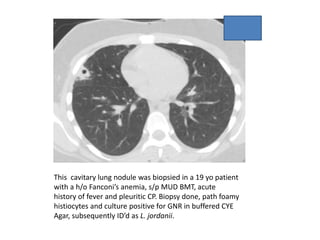

This cavitary lung nodule was biopsied in a 19 yo patient

with a h/o Fanconi’s anemia, s/p MUD BMT, acute

history of fever and pleuritic CP. Biopsy done, path foamy

histiocytes and culture positive for GNR in buffered CYE

Agar, subsequently ID’d as L. jordanii.

Legionella at MSKCC •Can cavitate in the immunocompromised host • Urine antigen detects only Type I (pneumophilia), which represents 95% of clinically significant Legionella isolates • The problem is: we see the other 5% here at MSKCC • Remember the micro lab: fastidious organisms often have different growth requirements

This cavitary lungnodule was biopsied in a 19 yo patient with a h/o Fanconi’s anemia, s/p MUD BMT, acute history of fever and pleuritic CP. Biopsy done, path foamy histiocytes and culture positive for GNR in buffered CYE Agar, subsequently ID’d as L. jordanii.